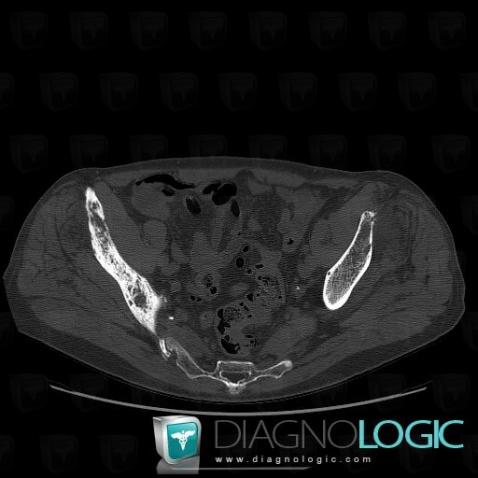

Metastasis, Ilium, CT

Here is the specific information in the key image above:

- Diagnosis Metastasis, Location(s) Ilium, with gamuts Generalised osteosclerosis